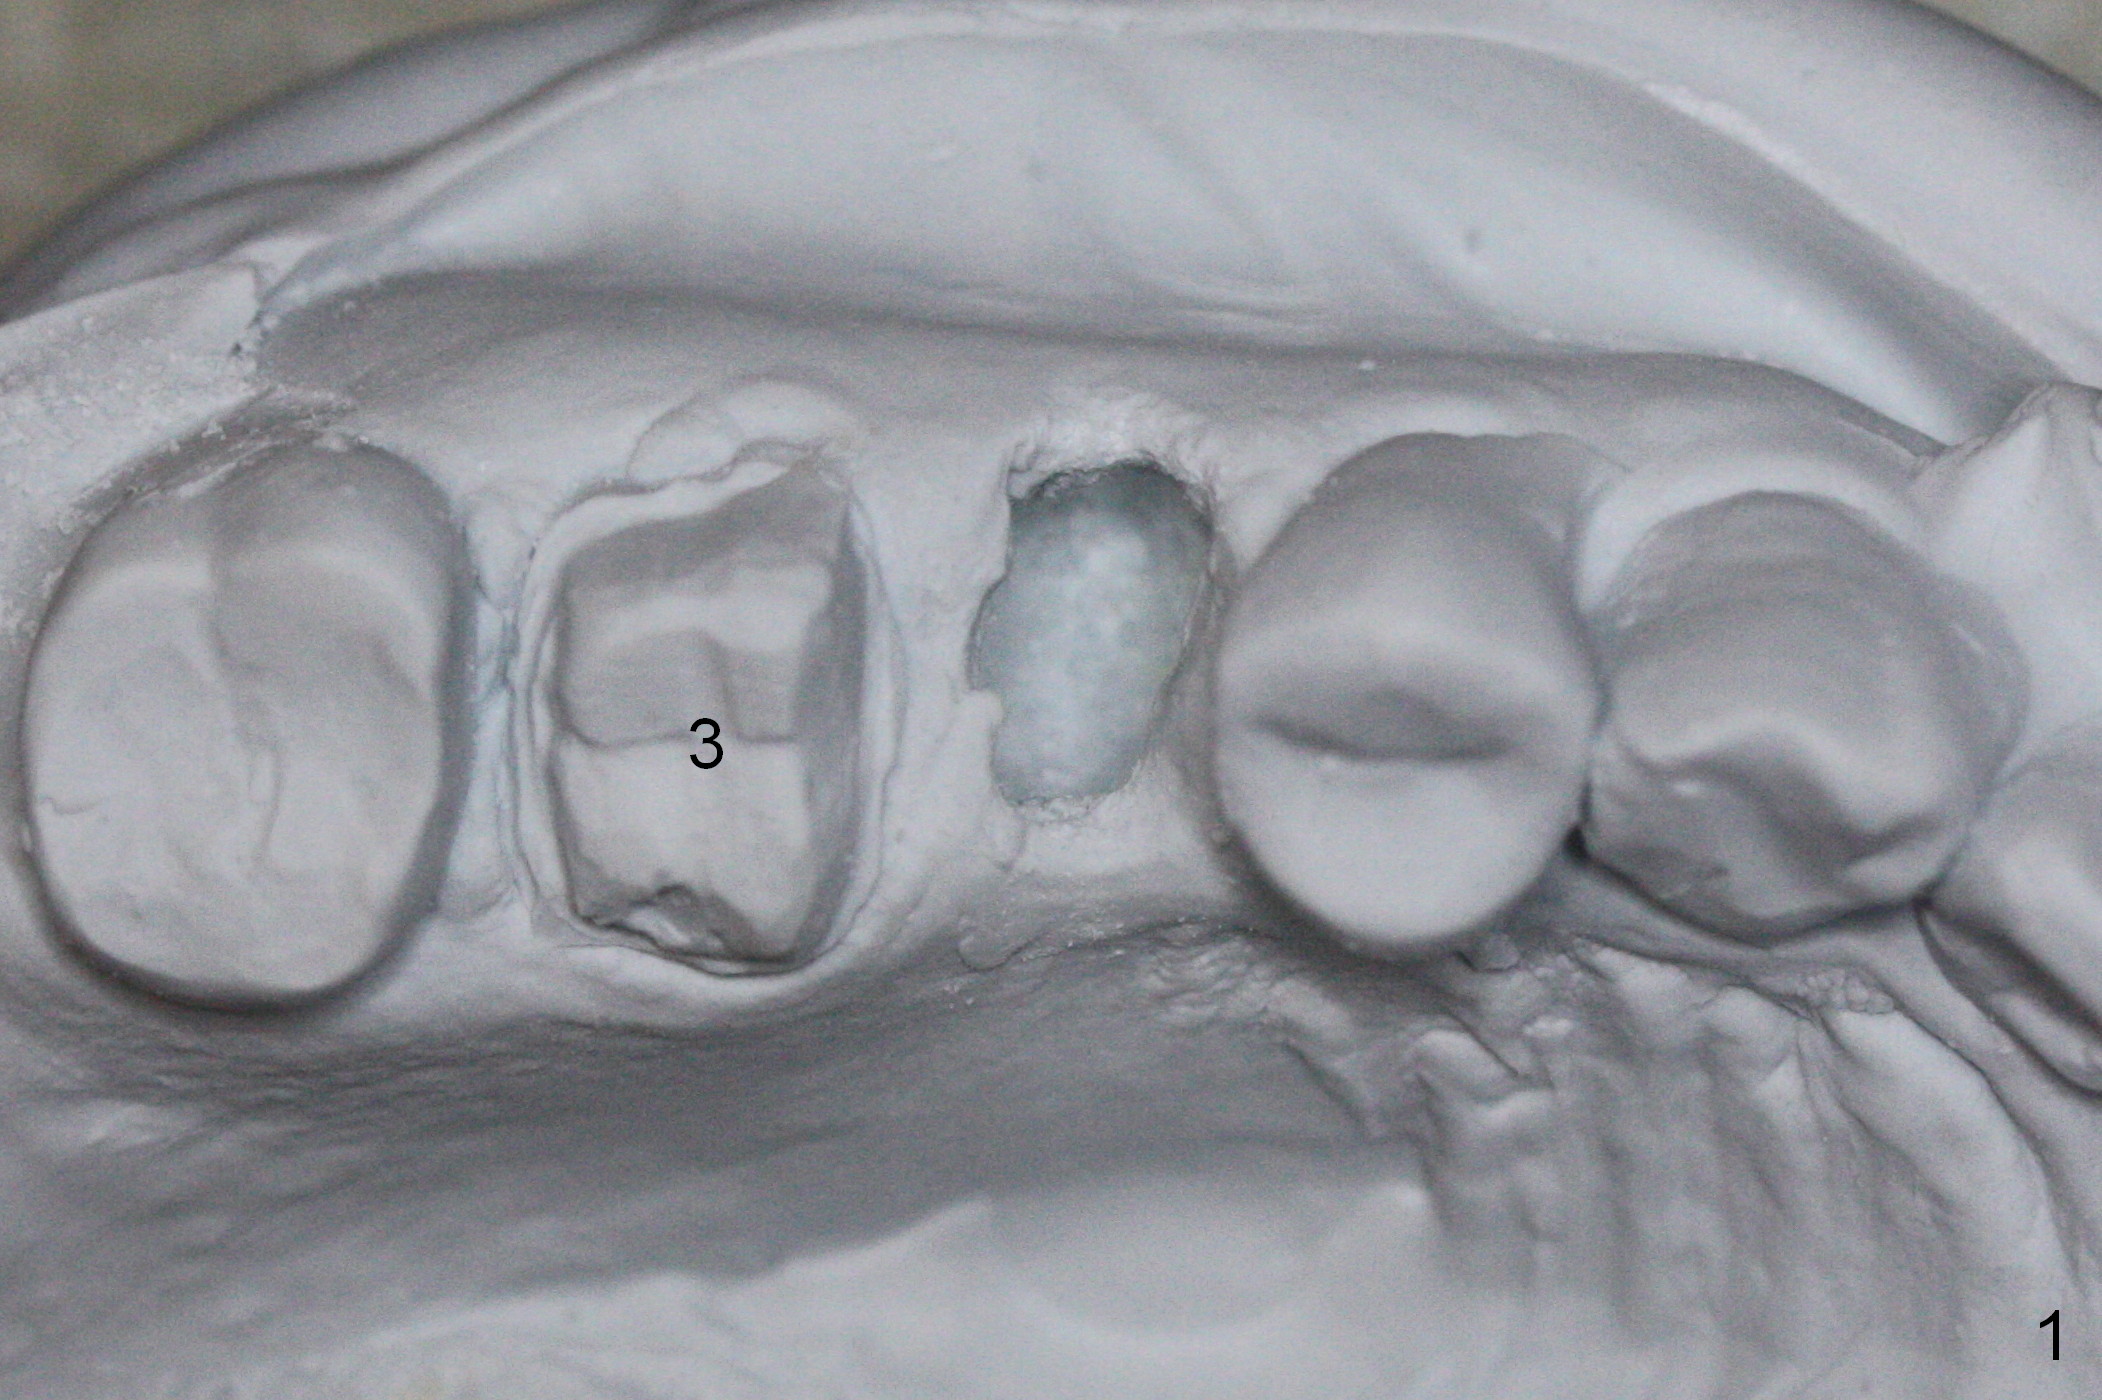

When the tooth #4 with vertical root fracture is extracted, the socket is large, approximately 6x10x10 mm (Fig.1 (mesiodistal x buccopalatal width x depth)). Osteotomy is established in the middle of the socket with 2 mm initial drill for 7 mm, 2.8 and 3.6 mm rounds drills (from DIO Sinus Master Kit) for < 7 mm, and 3.0 and 3.8 mm Magic Expanders. A 4x11 mm dummy implant is placed with insertion torque of 30 Ncm (Fig.2,3 (^: sinus floor)). There is a gap between the socket wall and the implant (*). To reduce the gap and periimplantitis, a 5x11 mm IBS implant is placed with insertion torque > 50 Ncm after further osteotomy using Magic Drills (Fig.4,5). Following placement of 5.5x4(4) mm abutment (A) and bone graft (data not shown), a splinted provisional is fabricated at #3 and 4. The provisional is stable 3 months postop (Fig.6,7). The peri-implant gaps (Fig.4,5) seem to disappear (Fig.6) with the help of bone graft. Bone graft appears to remain between the implant fins (Fig.7 arrows). Impression is taken 4.5 months postop (Fig.8,9). The abutment dislodges 4 months post cementation. After retightening, there is clearance for shim after use of 2 layers of thick articulating paper. Is the abutment screw too short? Or Titanium V is too hard for welding? The abutment/crown dislodges again 1 year 3 month post cementation; it appears that the fact that the implant is placed deep contributes to abutment screw loosening (Fig.10,11). An abutment screw will be buried inside the implant well 10 days post initial retightening.